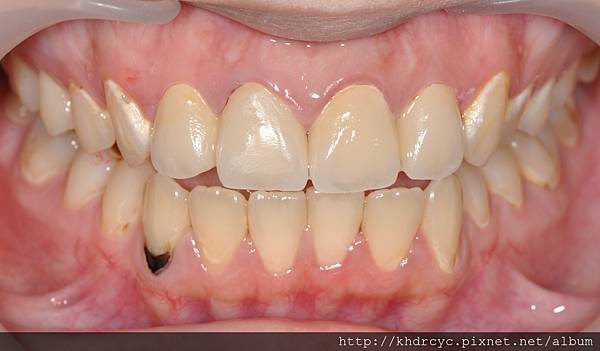

配合療程仁武的C小姐裝上全瓷假牙套

美觀立刻得到改善

等待門面牙肉與全瓷假牙貼合的過程

療程持續幫助仁武的C小姐蛀牙填補

與製作全瓷貼片繼續改善美觀